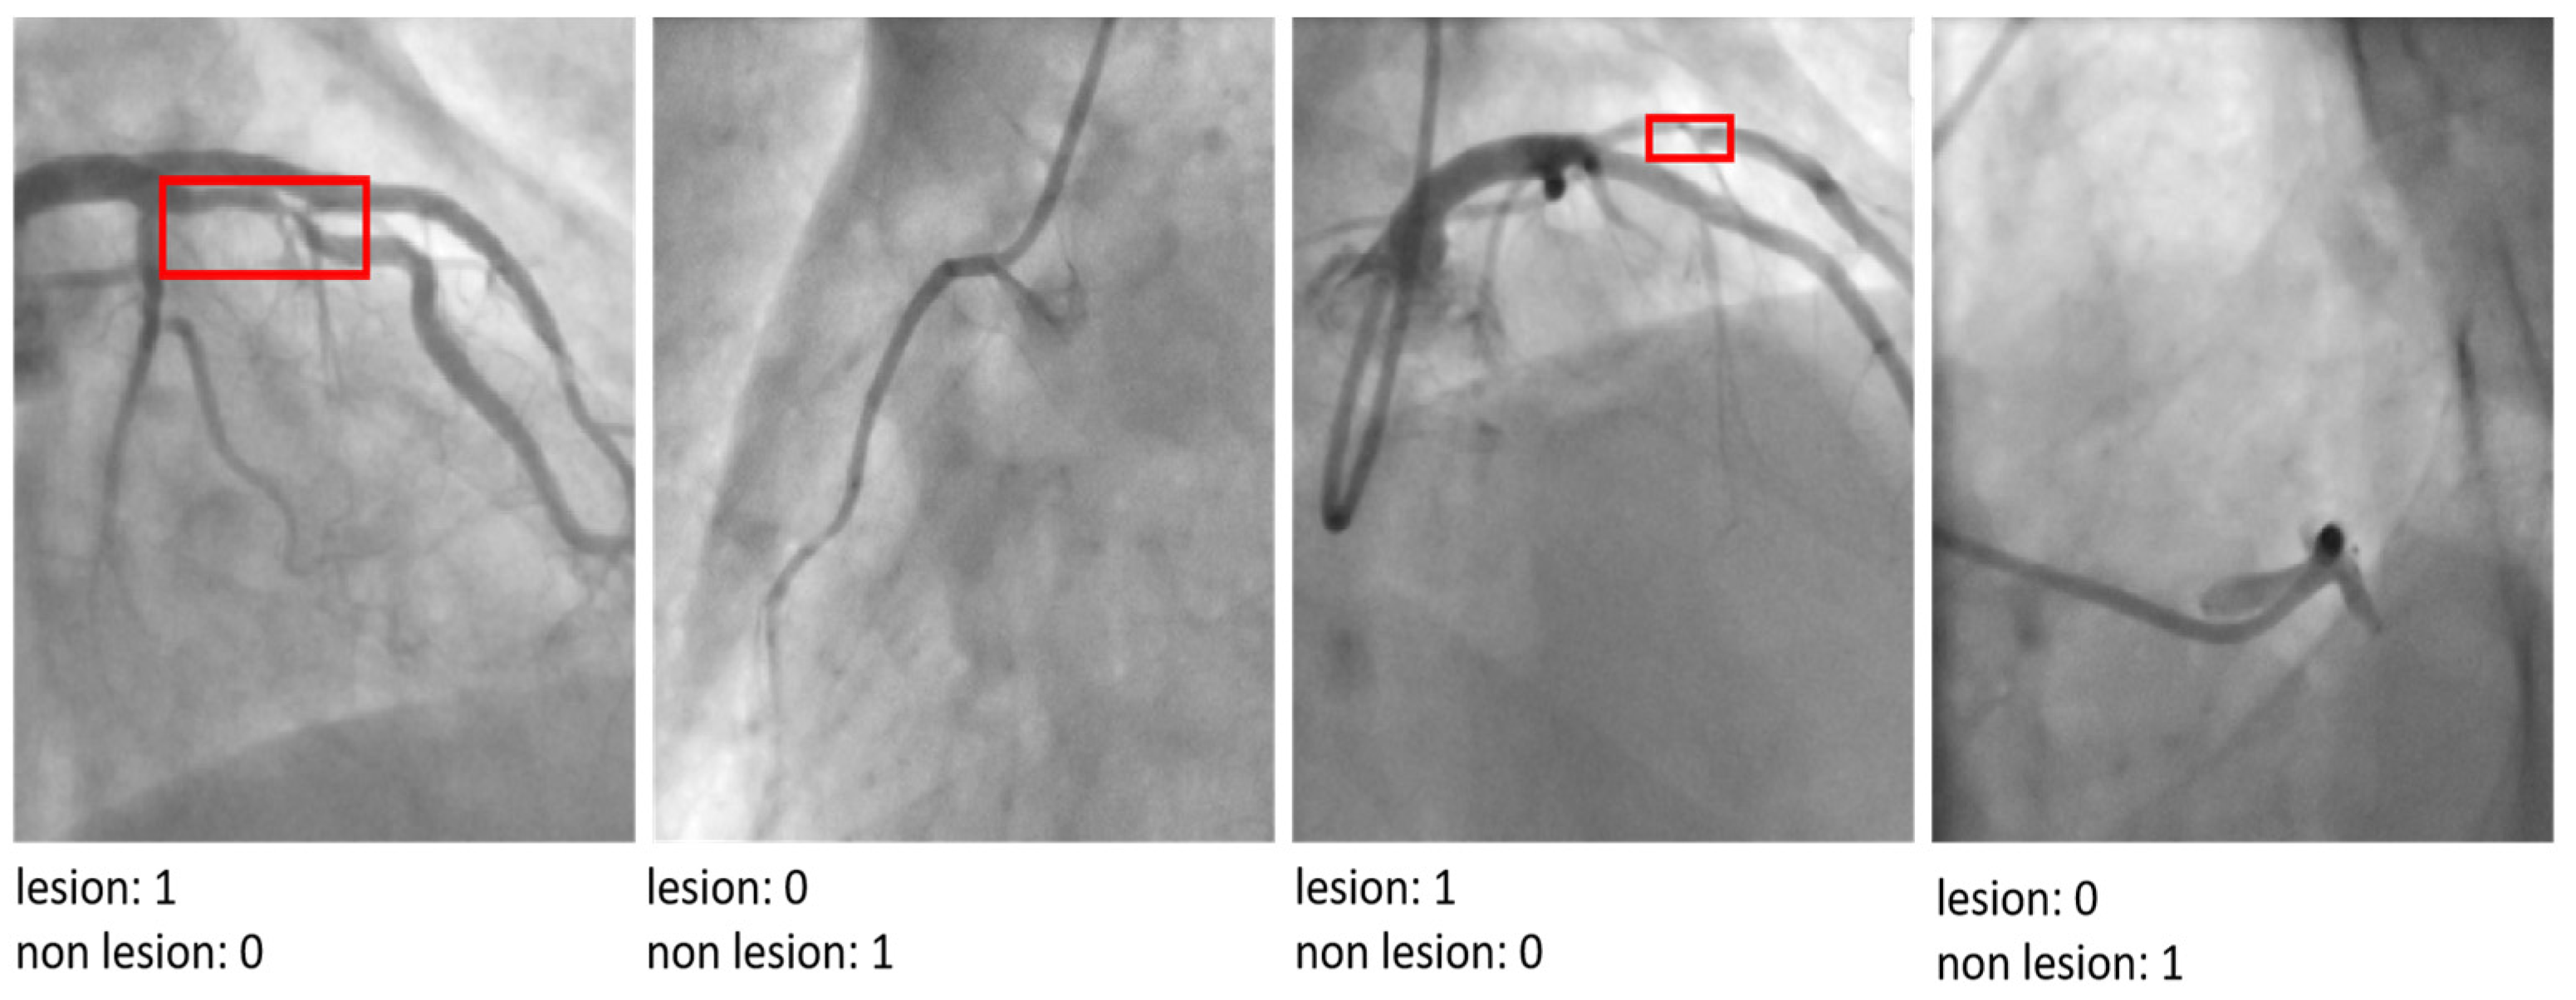

| Loss Function | Binary Cross-Entropy | Suitable for binary classification tasks like lesion detection (lesion vs. non-lesion). |